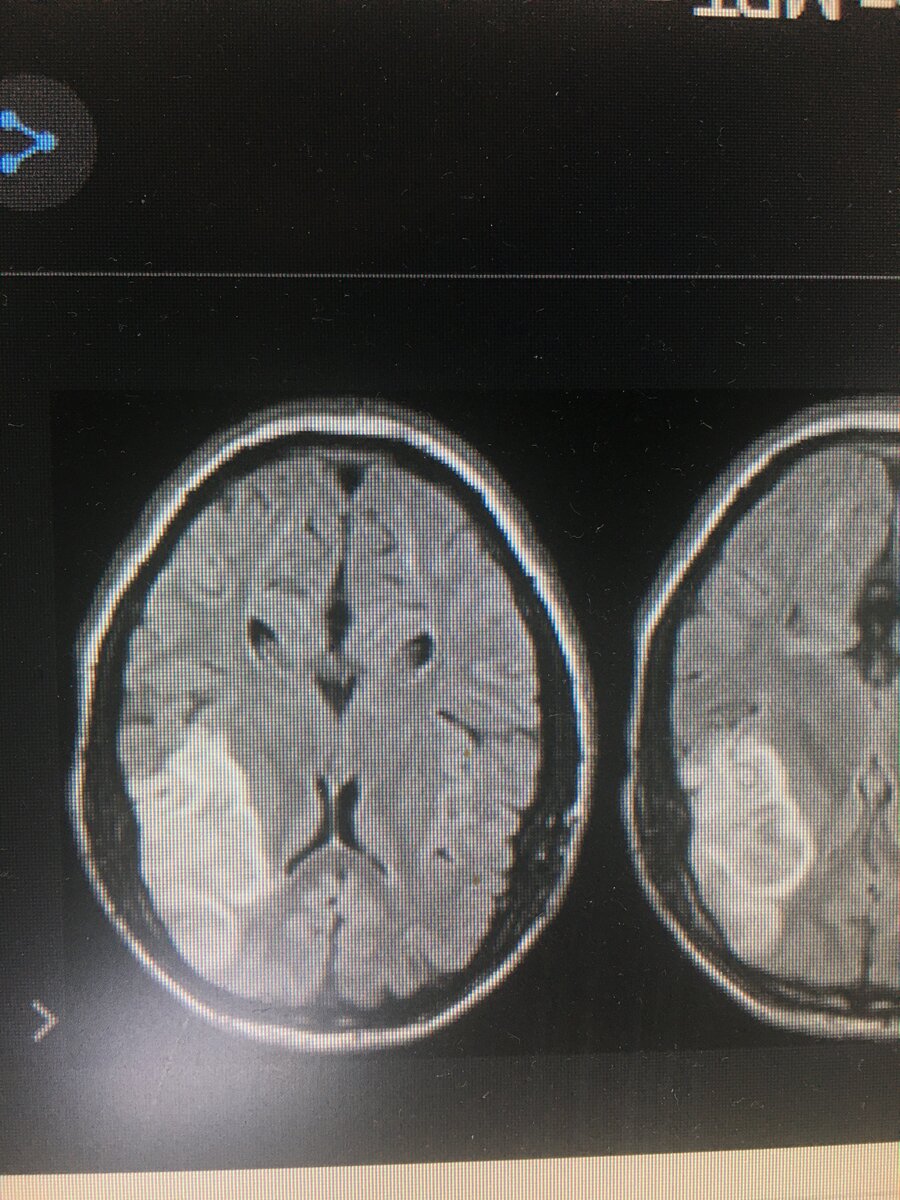

рабочие недели я уезжал с работы, и забирал все эмоции полученные в этом центре с собой, а хороших эмоций там было минимально, приходит человек, лет 20, которому доктор назначил МРТ головы. Из жалоб - сильное головокружение, онемел язык. На выходе у молодого человек диагноз «Инсульт» Инсульт на МРТ снимках

Инсульт на МРТ снимках